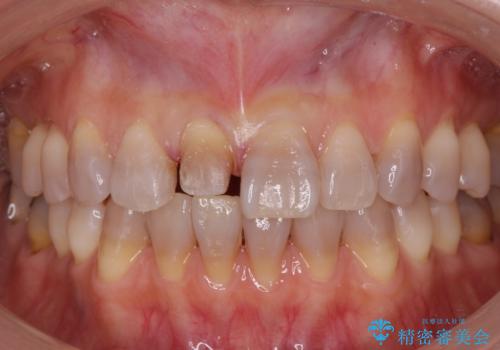

転んで前歯が折れた 色合いの難しい歯のセラミック修復

テトラサイクリン歯といって縞模様の強い歯の色調再現を行いました。

まず保険治療でコンポジットレジン修復を行い、神経の状態を確認した後、クラウンによる修復を行いました。